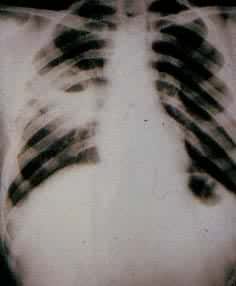

肺部疾病(一) 肺部疾病(二) 大叶肺炎 小叶肺炎 间质性肺炎 肺脓肿(正位) 肺脓肿(侧位) 支气管扩张 浸润性肺结核

肺结核空洞 肺不张